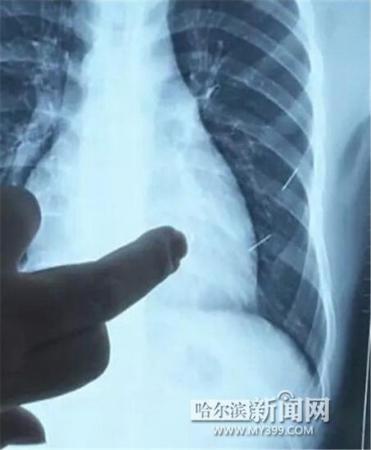

醫(yī)生指出X光片上的針狀物

昨日上午,記者在哈醫(yī)大二院第八住院部心外三病房找到了躺在病床上痛苦不堪的董立仁,家屬正在他身旁不斷安慰著他。見記者前來,董立仁母親李百燕拿出一張X光片,上面可以清晰地看到胸腔內一共有4根針狀物,其中一根在心臟部位,兩根在胸腔壁上,還有一根在腹腔壁上。